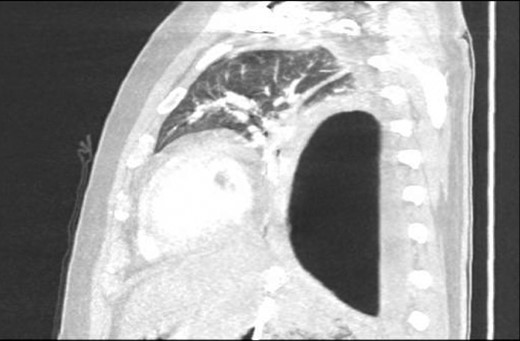

An Intercostal drain was inserted under CT-guidance aiming to decompress the pleural space. Amylase level in the pleural drainage was 880 U/l, Lipase 472 U/l. There was significant reduction of the Hydropneumothorax (Fig. 5). Given his young age, potential for loss of lung volume and infection he proceeded to decortication.

Sagittal view CT Chest post-intercostal catheter drainage of the Pancreatico-pleural fistula. Smaller residual space can be noted compared to Image 3, with some ongoing loss of lung volume and small fluid collection.